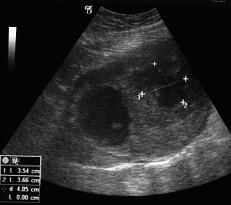

A 28-year old patient presented with acute abdomen due to hemoperitoneum from a large mass arising of the small intestine with distended vessels on its top and a ruptured superficial vessel bleeding into the peritoneal cavity. The patient was at the tenth postpartum day of her first pregnancy. The preoperative diagnosis was a possible ovarian or uterine mass. After an emergency exploratory laparotomy a segmental bowel resection was performed, removing the tumor with a part of 3-cm of the small intestine. Histology revealed GIST with maximum diameter of 13 cm and mitotic rates more than 5 mitoses per 50 high power fields with some atypical forms, indicating a high risk malignancy. Immunohistochemical staining of the tumor tissue demonstrated strongly positive reactivity to CD 117 (c-kit) and CD34 in almost all the tumor cells. The patient was treated with oral imatinib mesylate (Gleevec) 400 mg daily for one year. Three years after surgery, the patient was alive without evidence of metastases or local recurrence.

一位 28 岁患者因大量小肠肿块导致的腹腔积血而出现急腹症,肿块表面血管扩张,浅层血管破裂,血液流入腹腔。患者处于首次妊娠的第 10 天产后期。术前诊断为卵巢或子宫肿块的可能性较大。在紧急剖腹探查术后,进行了一段肠切除术,切除了肿瘤和部分 3cm 小肠。组织学显示 GIST,最大直径为 13cm,每 50 个高倍视野中有超过 5 次有丝分裂,存在一些非典型形态,提示高度恶性肿瘤。肿瘤组织的免疫组织化学染色显示 CD117(c-kit)和 CD34 在几乎所有肿瘤细胞中均呈强阳性反应。该患者接受了每日 400mg 甲磺酸伊马替尼(格列卫)的口服治疗,持续一年。术后 3 年,患者无转移或局部复发的证据,存活至今。